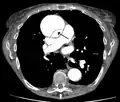

Dissection of the descending part of the aorta (3), which starts from the left subclavian artery and extends to the abdominal aorta (4). The ascending aorta (1) and aortic arch (2) are not involved in this image.